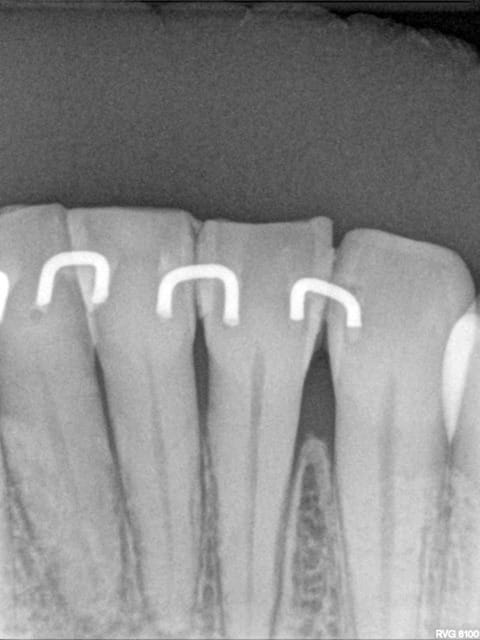

Les attelles d'Abjean j'en pose chaque semaine (ou presque), l'avantage ENOOOOORME par rapport à un "jonc noyé" c'est la rétention 3D que tu n'as pas avec le jonc!

et le délabrement est bcp moindre, en plus quand une attelle lache tu la changes, et pas tout le bastringue!

1) les forêts drill: tu as quelle réf. ???

2) le fil c'est du jonc en 0,8 mm

3) tu fais une gorge horizontale reliant les 2 points de contact jusqu'à la dentine (prof 1 mm) fraise HL 008

4) un léger avant trou à la fraise boule 008 aux extrémités de la gorge (komet H 009)

5) forage basse vitesse prof 1 à 2 mm les puits doivent être le plus parallèle possible (dans le tiers proximal de la dent à distance raisonnable de la pulpe ;-)

6) confection de l'attelle grâce à une pince à bec plat fine modifiée qui te permet de faire toutes les tailles d'entre-axe

7) essayage et puis souvent réessayage et scellement ou collage si tu en as.

C'est comme cela que Le Pr José Abjean nous l'a appris...à la fac.

C'est joli, mais je trouve que sur les radio, les trous sont plus prodonds que la contention et je trouve cela invasif vs fil ou contention classique. Pour quelques cas bien précis, ok, mais pas trop fréquente l'indication non ?

Ben si en fait, c'est la seule:

1 a être discontinue (donc refaisable sans tt déposer encore une fois)

2 a avoir une rétention axiale, vestibulo palatine, et disto mésiale (3 axes)

3 assez facile à mettre en oeuvre (par rapport à la manipulation d'un long fil que tu colles d'un bout qu'il faut tenir pour ne pas qu'il bouge :(....

4 délabrement moins important et risque de fracture de la dent bcp moindre (bord incisal par exemple)

5 résultat immédiat esthétique et absence d'interférences occlusales car entièrement incluse dans les puits et sillons réalisés.